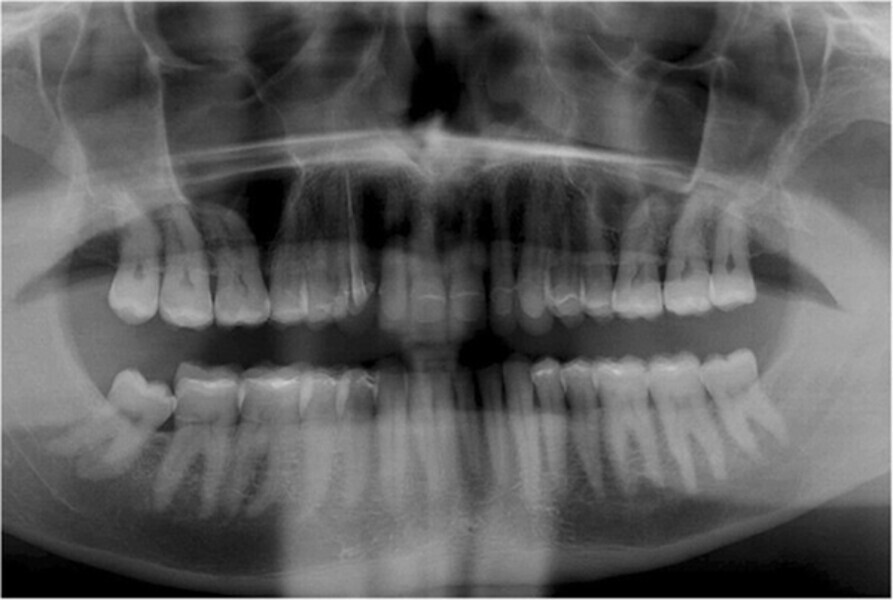

Fig. 2. Situación inicial, radiografía panorámica (2015).